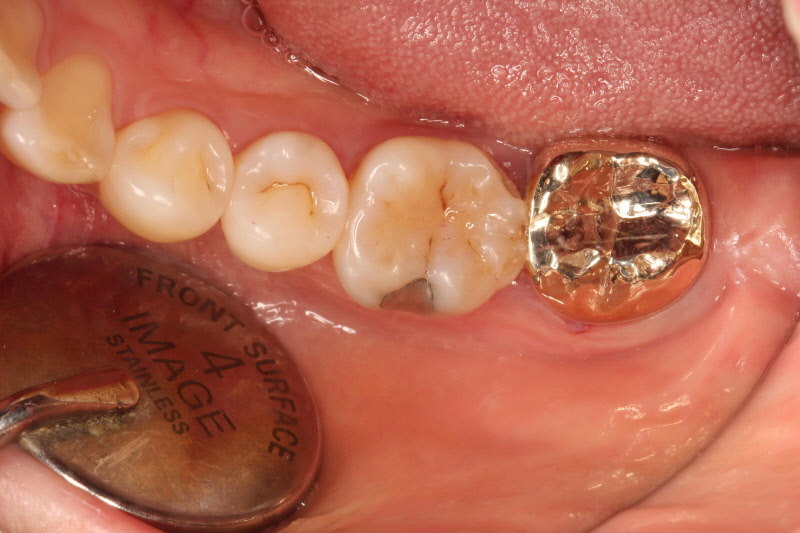

가끔은 충치가 너무 진행이 되어 신경에 문제가 되는 경우도 있는데 이런 경우는 신경치료를 먼저 시행하고 그 다음 크라운으로 치아를 보호해 주는 방식으로 치료 되어야 합니다. 크라운의 재료로는 금과 도자기를 들 수 있습니다. 금 크라운은 씹는 충격 등에 강하고 치아를 삭제하는 양을 조금 줄일 수 있으며, 향후 생기는 변화에 적응되는 능력이 뛰어납니다. 단점으로는 금색이므로 예쁜 모습이 필요한 부위에 적용할 수 없으며, 열의 전달이 빨라 씌운 후 경우에 따라 당분간 좀 더 시릴 수 있습니다. 시간이 지나면 시린 부분은 많이 감소하게 됩니다.

금을 이용한 크라운